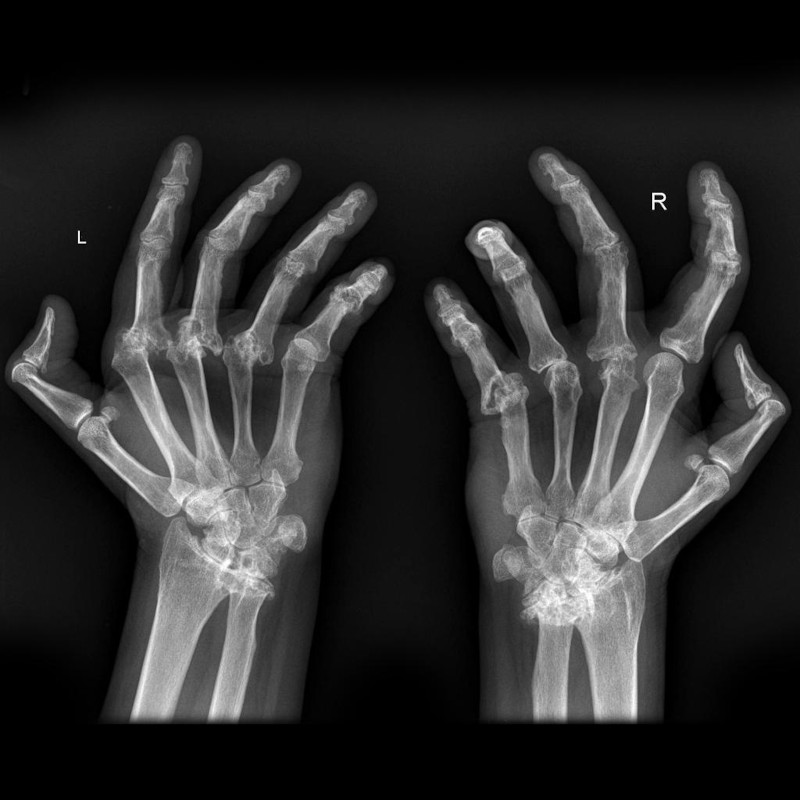

Esistono oltre 100 tipi di artrite e le forme più comuni sono l'artrosi (malattia degenerativa delle articolazioni) e l'artrite reumatoide. L'artrosi di solito si verifica con l'età e colpisce le dita, le ginocchia e le anche. L'artrite reumatoide è una malattia autoimmune che spesso colpisce mani e piedi. Altri tipi includono gotta, lupus, fibromialgia e artrite settica. Sono tutti i tipi di malattie reumatiche.

Sintomi e Segni

Il dolore è il principale e può variare, ma sempre presente. L'altro sintomo importante è il gonfiore, rigidità articolare, rossore e dolore attorno all'articolazione. Questi sintomi possono portare a:- Inabilità ad usare le mani o a camminare